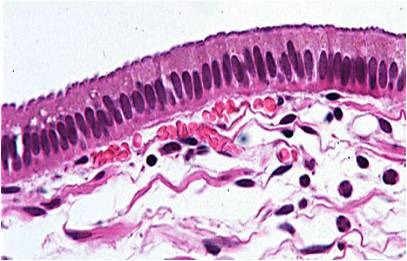

pseudostratified columnar

appears layerd but consist of cells all attached to a basement membrane; commonly have cilia and goblet cells found in respiratory tract